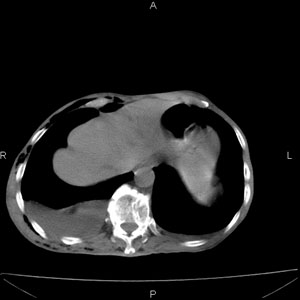

患者男,77岁,于3日前从树上摔下,头部查ct示蛛血,硬膜下出血,上腹部ct未见明显异常,右侧胸腔积液,左侧如常。肺部拍片示右侧肋骨多发骨折住院后今日来查肺部ct,我看到的是1。右侧胸腔血气胸并右肺上叶,中叶压缩性肺不张,2。右肺下叶肺挫伤并多发肋骨骨折,肌内及皮下积气3。左侧少量胸腔积液,我想请教的是3天前左侧胸腔里没有积液今天怎么出现了呢,是什么原因呢?请讨论。

右侧液气胸,胸膜创伤、肺组织挫伤,渗出属正常反应。